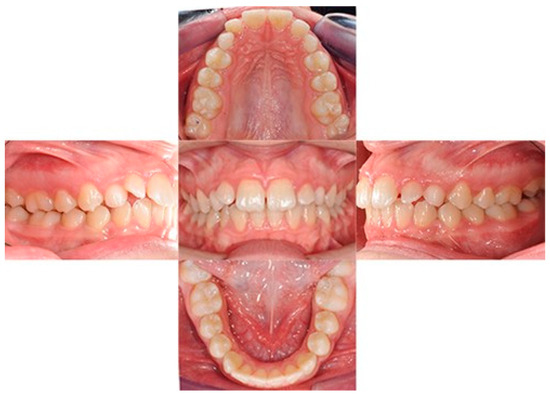

The treatment duration was 26 months. The post-treatment facial photographs showed a nicely balanced and harmonious face. A class I occlusion was obtained, and a distal space resulted in the upper incisors due to Bolton discrepancy. Prosthetic restoration was programmed to complete the patient’s smile. According to Table 1, counterclockwise rotation of the mandible was achieved (Figure 11, Figure 12 and Figure 13).

Figure 11. Final intraoral photos.